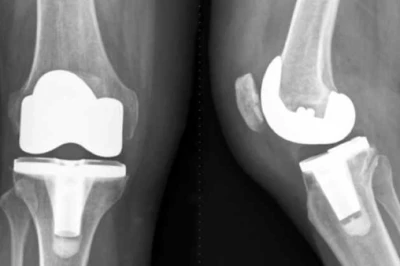

9 بهمن 1404 بررسی روشهای جلوگیری از ترومبوز وریدی پس از آرتروپلاستی | پیشگیری و مراقبت پس از جراحی زانو